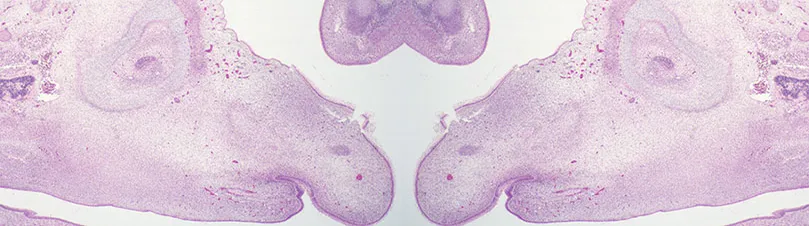

Equine embryo head